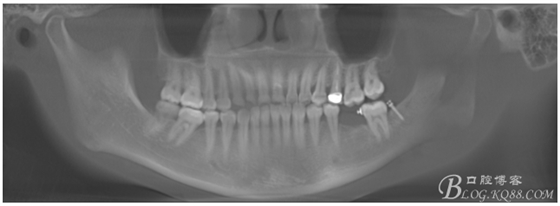

檢查:36.46缺失,36缺牙區(qū)近遠中間隙約3mm,46缺牙區(qū)間隙約0.5mm,37.47.48近中傾斜,48近中面齲壞達牙本質淺層,37牙周探診4mm,47近中探診深度5-6mm,不松,口內照片及CT片如下:

術前CT